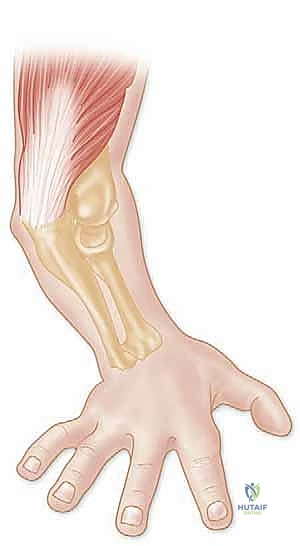

لا تحدث إصابة الثالوث الرهيب نتيجة التواء بسيط، بل تتطلب قوة ميكانيكية محددة وعنيفة. الآلية الأكثر شيوعاً هي السقوط على يد ممدودة (Fall On an Outstretched Hand - FOOSH).

عندما يسقط الشخص ويهبط على كف يده وذراعه مفرودة، تنتقل طاقة السقوط الهائلة عبر عظام الساعد لتصطدم بمفصل الكوع. تحدث الإصابة وفق تسلسل حركي معقد يتضمن ثلاث قوى متزامنة:

1. التحميل المحوري (Axial Loading): وزن الجسم يضغط بقوة عبر الذراع نحو الأرض.

2. إجهاد الإبهام (Valgus Stress): انحناء الكوع نحو الداخل بقوة تفوق قدرة الأربطة على التحمل.

3. الاستلقاء (Supination): دوران الساعد للخارج بقوة.

هذا المزيج القاتل من القوى يؤدي إلى تمزق الكبسولة المفصلية والرباط الجانبي الوحشي (LCL) أولاً. مع استمرار القوة، ينزلق الكوع للخلف، وتصطدم عظمة رأس الكعبرة بعظمة العضد بقوة هائلة مما يؤدي إلى كسرها. وفي اللحظة ذاتها، ينحشر الناتئ الإكليلي لعظمة الزند تحت عظمة العضد وينكسر. أخيراً، تتمزق الأربطة الإنسية (MCL) أو تُقلع مع قطعة العظم المكسورة، ليكتمل بذلك "الثالوث الرهيب".